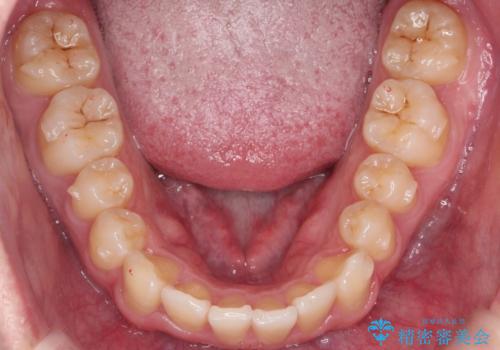

- 前歯のすきまと八重歯を主訴に来院。

左上の乳犬歯が残っており、その下から生えてくるはずの犬歯(永久歯)が左上小臼歯部に萌出していました。

左上の乳犬歯は根もしっかりしていたため、

➀そのまま矯正する。乳歯がいずれダメになったときにそこはブリッジかインプラントを検討する

②乳歯は抜歯し、ブリッジかインプラントを矯正後に入れる

を提案し、➀を選択されました。

将来的にインプラントは希望されないとのことだったため、乳歯の部分は隙間を開けてインプラントを入れる用のすき間を確保するということは特に行いませんでした。

乳歯をそのまま並べたため、上顎の左右の犬歯の幅は非対称になっています。